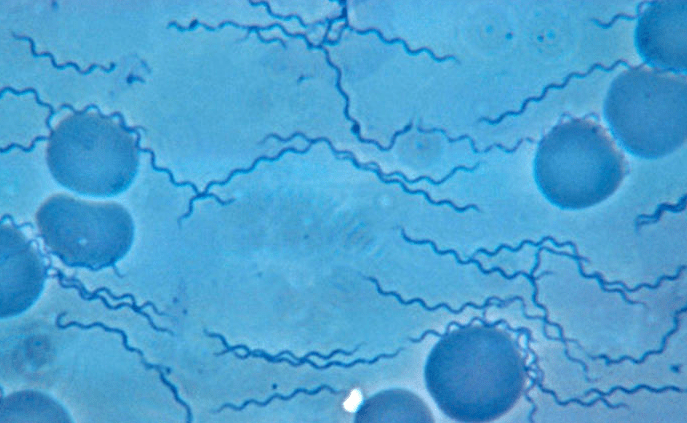

Bild på Borrelia recurrentis

Lusburen återfallsfeber – Borrelia recurrentis

referensmetodik sker genom mikroskopiskt påvisande av spiroketerna i blod.